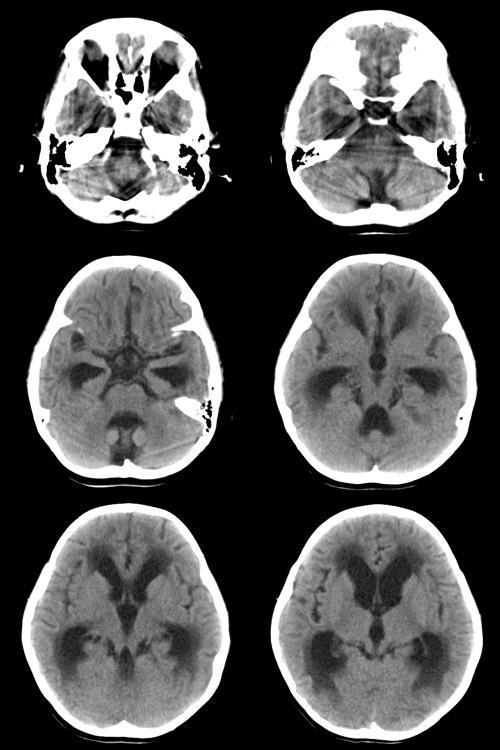

标题: PED1843:患者女,4y,脑积水。

4岁女性,精神差,间断呕吐4+月。加重并右侧肢体肌力减退10+天,行走困难。无发热、无意识障碍。4个月前患儿无异常表现,读幼儿园。

请问有经验的老师,这种情况最可能是由什么疾病引起的?